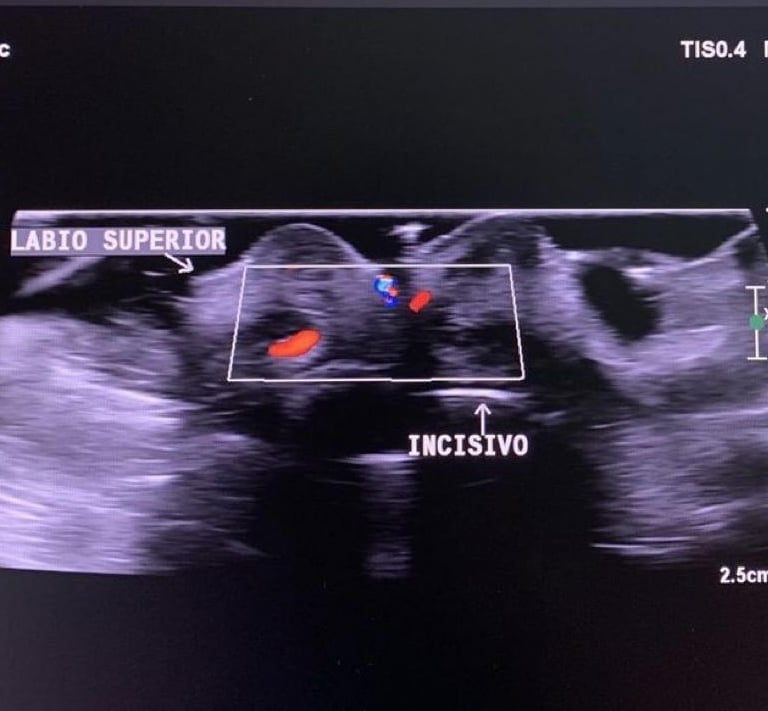

CEO da EccoFace.Formada em Odontologia pela Universidade Católica de Brasília em 2004, Pós-graduada em endodontia,odontologia Intensiva,Oncologia( Sirio Libanês) e Harmonização Orofacial. Mestranda em Radiologia odontologica com foco em Ultrassonografia Facial.